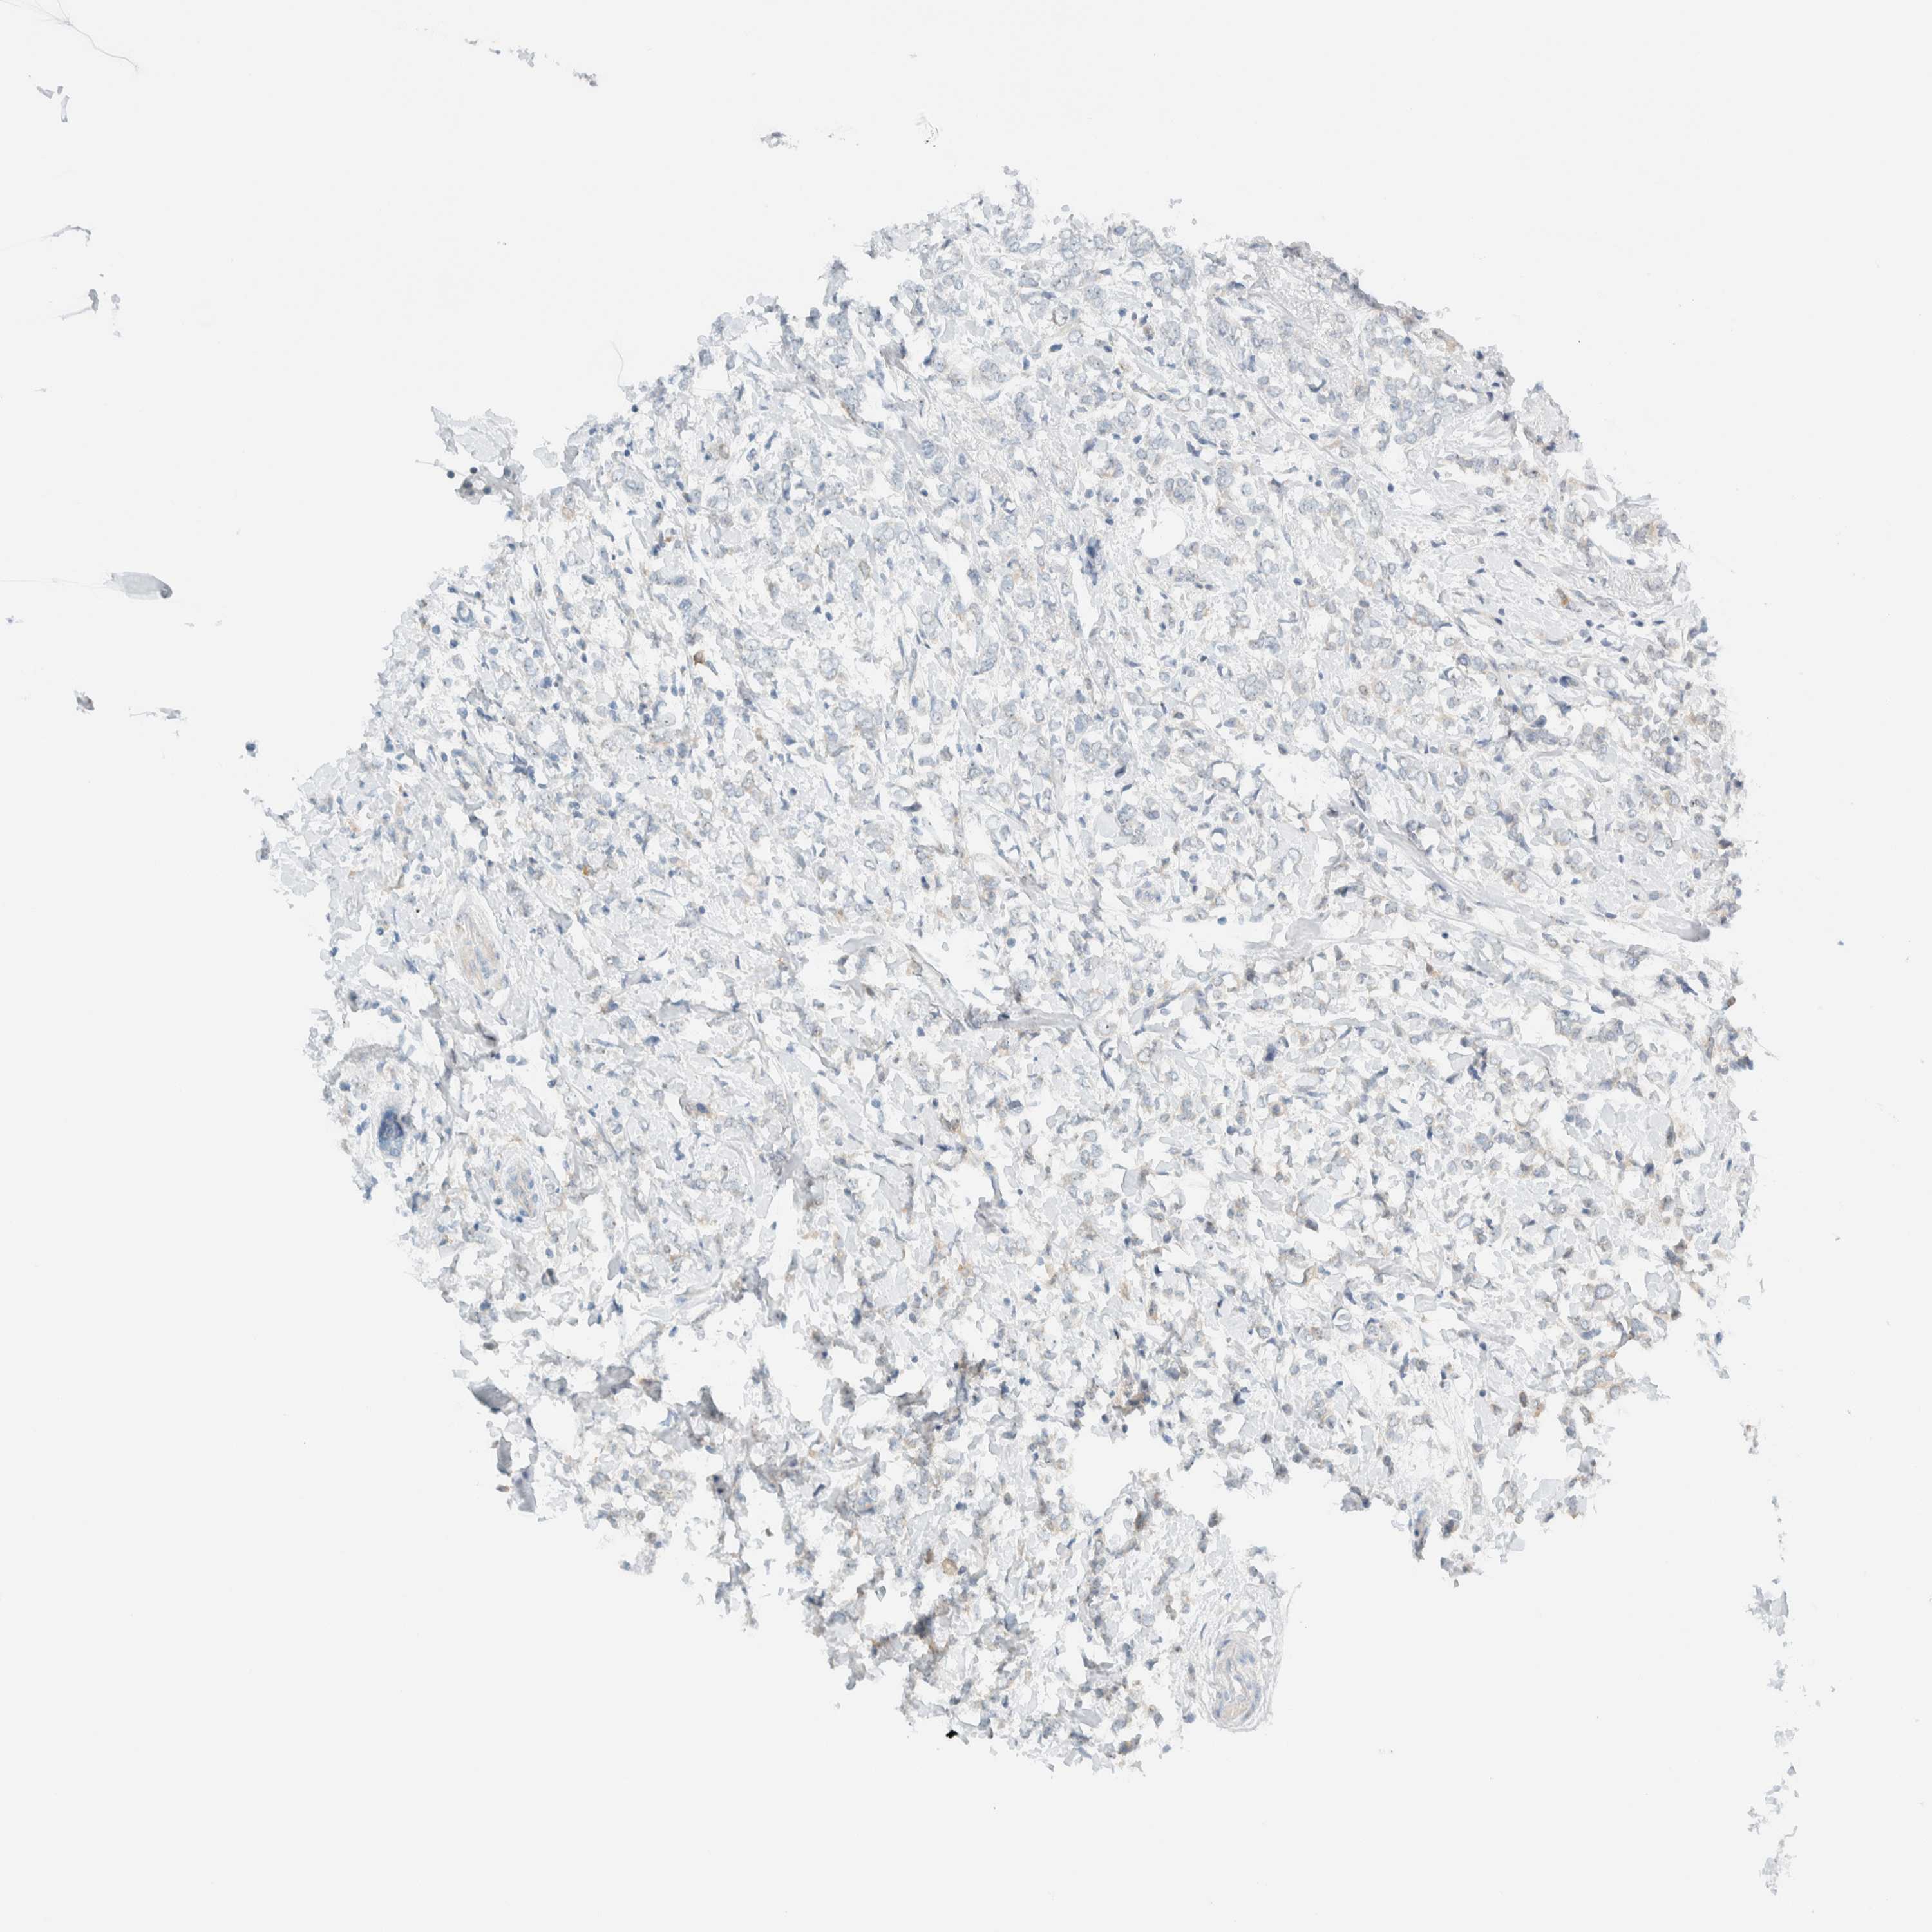

CANCER BREAST CANCER Show tissue menu

BRCA TCGA BRCA VALIDATION PROTEIN EXPRESSION